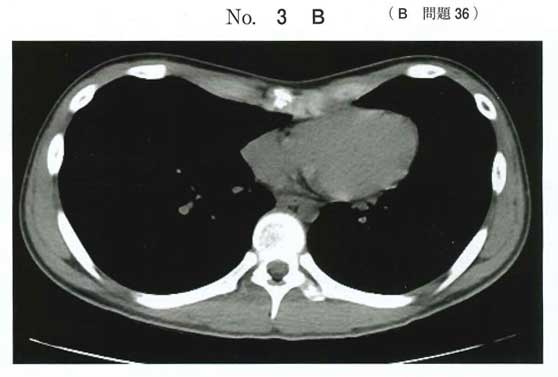

今回の提示画像(X線+CT)と設問文脈(胸郭変形の相談)からは、漏斗胸=胸骨の陥凹(b)が適切

b:漏斗胸

漏斗胸手術(ナス〈Nuss〉法:胸腔鏡を使用しステンレスバーを体内の適正な位置に留置し、漏斗胸を整復する)を実習で見学したことがあります